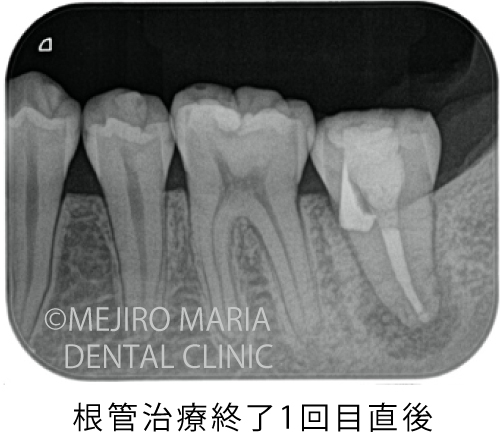

今回は根管形態が複雑ではなかったため、初回で根管内をすべて洗浄後、根管充填と穿孔修復(パーフォレーションリペア)を行い、2回目の治療にて、歯の土台を作る支台築造処置を終了させました。

根管治療終了1ヶ月後に経過観察を行い、術前に確認されていた限局的な歯周ポケットは正常範囲まで回復したのを確認しました。2ヶ月後にはレントゲンにて歯の根の先に見られた黒い透過像の縮小も確認できたため、仮歯を作製し、問題がなければ最終補綴に移行する予定です。